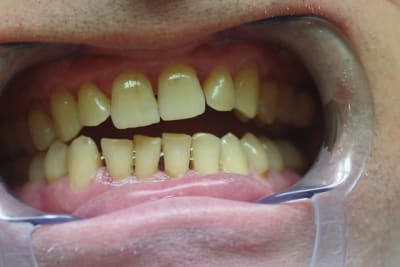

Le patient de 65 ans n'a plus d'occlusion sur le secteur ant et sur le secteur postérieur gauche.

L'occlusion ne se fait que sur les 5, 6 et 7 côté droit.

J'ai d'abord pensé adresser le patient pour une rééducation linguale ( kiné ou orthophoniste) car le patient a une langue très puissante qui a entraîné l'inocclusion totale des secteurs antérieurs et latéraux ( côté gauche).

Je pencherai plutôt vers une déformation de son maxillaire due à une pulsion linguale importante.

Les photos sont assez évocatrices car le plan de Fox mis à l'arcade supérieure montre nettement une divergence entre la ligne bipupillaire et le plan.

J'ai pris aussi une photo en demandant au patient de déglutir et on voit la langue qui s'interpose entre les arcades ( là où il y a béance).

Ce monsieur a une langue très présente (photo 2) => rééducation.